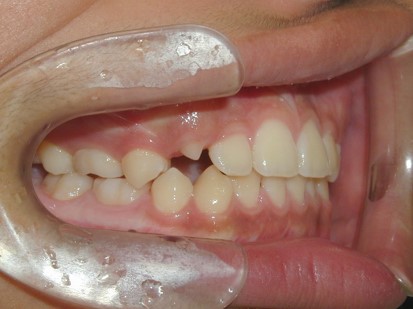

永久歯に交換するためのスペース不足による前歯のガタガタで、取り外しができる拡大床にて上下顎の幅を拡大した後、上顎の前歯をマルチブラケット装置で並べました。治療の期間は1年9か月でした。

初診時